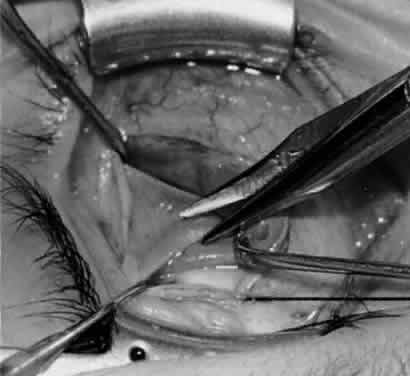

Fig. 5. The Stevens hook is placed adjacent to the posterior edge of the inferior oblique muscle and rotated as the inferior oblique muscle is drawn into the operative field. A forceps is used to retract the redundant Tenon's capsule, encapsulated fat, and intermuscular septum as the muscle is drawn further into the operative field with the Stevens muscle hook.

Fig. 6. The Westcott scissor is used to open the intermuscular septum along the posterior border of the inferior oblique muscle. Care is taken to cut adjacent to the tip of the Stevens muscle hook. This incision is important because it helps to avoid damaging the Tenon's capsule and releasing fat, which leads to the adherence syndrome and postoperative hypotropia.